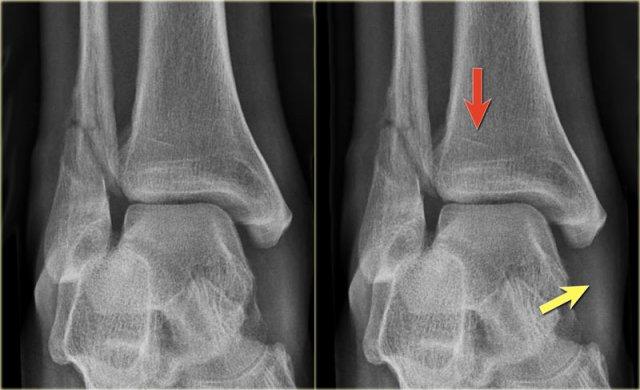

- Tái khám

Trên phim chụp cổ chân không có dấu hiệu gãy xương chéo của mắt cá ngoài, do đó chúng ta có thể loại trừ gãy xương Weber B.

Vẫn còn khả năng gãy xương Weber C giai đoạn 4, tức là đứt hoặc bong gân phía trong, gãy xương mác cao và cuối cùng là gãy mắt cá sau.

Khi tái khám, bạn nhận thấy hình ảnh bong điểm bám tinh tế của mắt cá trong (mũi tên đỏ), đây là giai đoạn 1.

Cũng lưu ý tình trạng sưng nề phần mềm ở phía trong (mũi tên xanh)

Các phim X-quang bổ sung của chi dưới được chỉ định và cho thấy gãy xương mác cao, tức là Weber C giai đoạn 3, còn được gọi là gãy xương Maisonneuve.

Final report

Weber C fracture stage 4.

This is un unstable ankle injury that needs surgical repair.